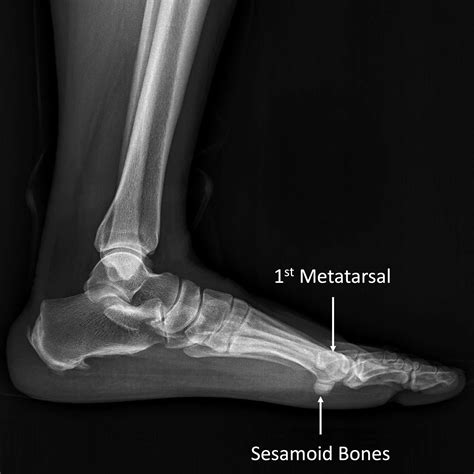

The sesamoid bones are small, round bones embedded within tendons. In the foot, there are two sesamoid bones located beneath the head of the first metatarsal bone, which is the long bone connected to the big toe. These bones are named the medial and lateral sesamoid bones, and they act as pulleys for the tendons that control the big toe.

• X-rays: To visualize the bones and detect any fractures or abnormalities.

• sesamoid bone foot xray